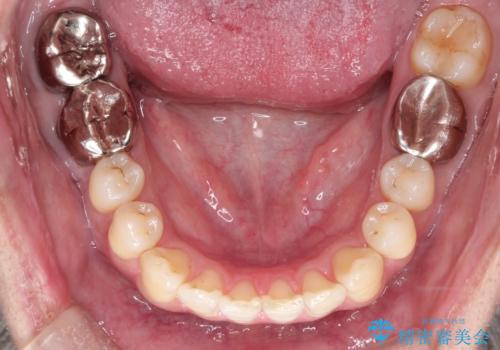

- 前歯の出ているのが気になる、下唇を噛んで痛いとのことで来院された患者様です。マウスピース矯正をご希望でした。

奥歯の噛み合わせはしっかりしていましたので、奥歯の動きは最小限にし、前歯の並びに集中した治療計画+インビザラインのシミュレーションを作成しました。

奥歯の噛み合わせは整っていたため、前歯の並びを美しく修正することに専念できました。マウスピース矯正による治療で短期間で改善しました。